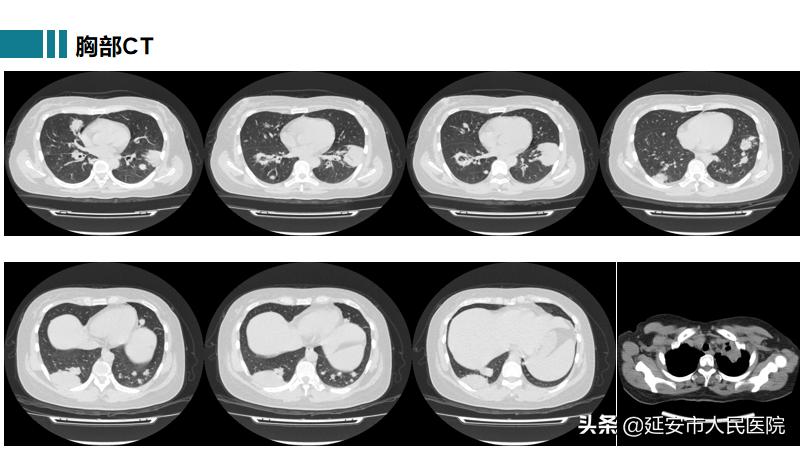

高院副主任医师接诊后,行胸部CT提示:双肺散在结节状高密度影,边界清楚,结节大小不等,部分结节内空洞形成;查体:右侧结膜充血,左侧外耳红肿、疼痛,双肺呼吸音粗,未闻及干湿啰音;化验血常规:白细胞8.7*109/L,血红蛋白96g/L,尿常规示隐血3+,D二聚体3310ng/ml,常规C反应蛋白127.54mg/L,血沉100mm/h。根据患者以上情况,首先考虑肺结核可能性最大,但患者病情进展较快,呼吸困难呈进行性加重,双下肢逐渐出现散在的出血点,不能用肺结核来解释,而且这样的胸部CT表现很少见到。面对如此复杂又难以解释的病例,高院副主任医师立即请中国医科大学驻延安医院副院长、医学博士、呼吸与危重症医学科学科带头人郑锐教授进一步诊断。

患者在最短时间被诊断为肉芽肿性多血管炎(GPA),转至风湿免疫科进行系统有效治疗后,患者精神状态好转,症状明显减轻,复查胸部CT双肺病变较前显著吸收,患者终于露出了久违的笑颜: “多亏了中国医科大学郑锐教授的一双‘火眼金睛’,帮我及时确诊了病情,让我得到有效的治疗,真的太感谢郑教授了。” 目前,患者已好转出院,后续仍在治疗中。